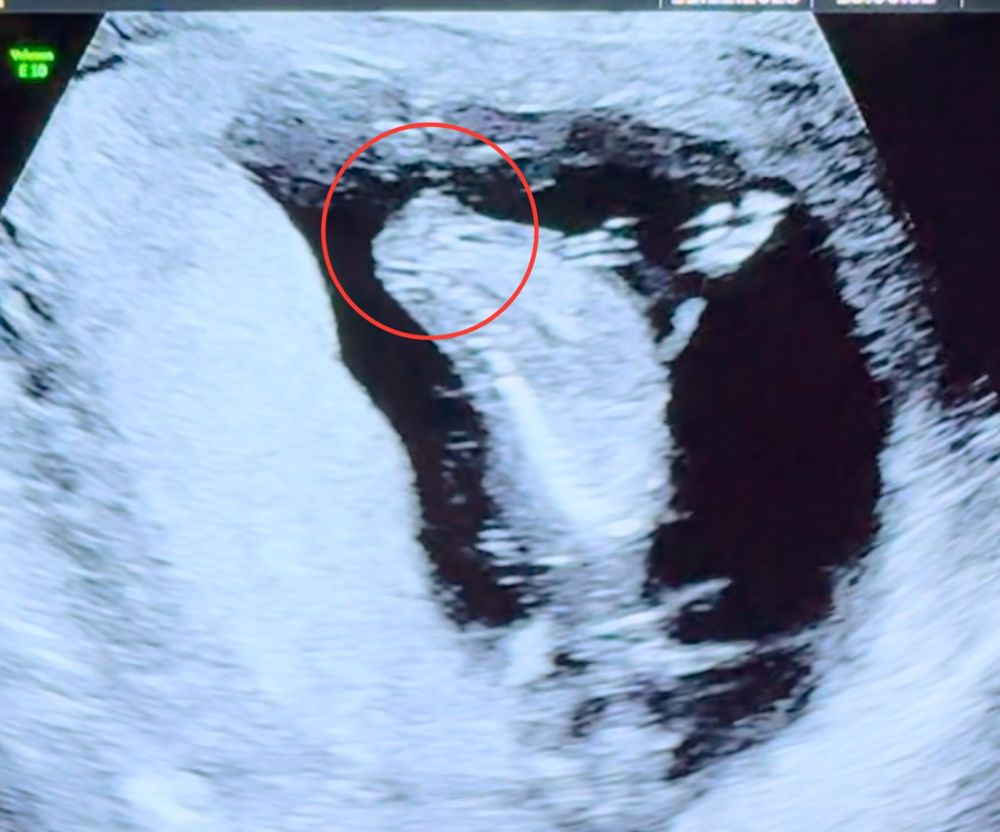

Девчушка, у вас прям четко видно что девочка, на последней фото где боком лежит и ножки поджаты 🙈 если бы был мальчик что торчал бы писюн хоть чуть чуть, а тут гладко все)

Анастасия, "писюна" в 13 недель ещё нет) на этих неделях идёт активное формирование половых органов) поэтому ваше в 15, нельзя сравнивать с узи в 13) по крайней мере, так гласит литература) в 15-16 да, уже все видно)

Яна, я говорю это как человек который имеет образование в данной сфере и знания)) по этому я смело предполагаю что тут девочка) опытные врачи по бугорку который все же имеет различия на 13 неделе могут определить пол малыша

Летта, мне вот тоже кажется, что мальчик. Мне когда с дочкой узи делали, там прям белая такая полосочка длинная была, узист мне ее показала и сказала, что девочка. А тут не вижу полоски))) Но я не эксперт по узи 🤣